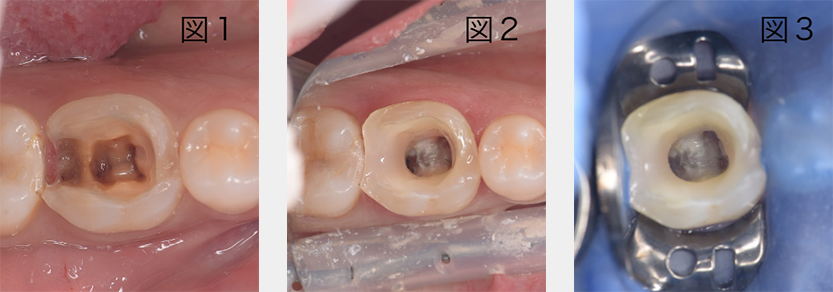

隔壁の作成とラバーダムの装着

図1の状況で根管治療を行うと、細菌が大量に含まれている唾液が根管内に流入してしまうため、成功率が低下します。図2のように隔壁を作成してからラバーダムを装着すると(図3)、無菌環境での治療が可能になります。精密根管治療においては、徹底して隔壁の作成とラバーダム装着を行っております。